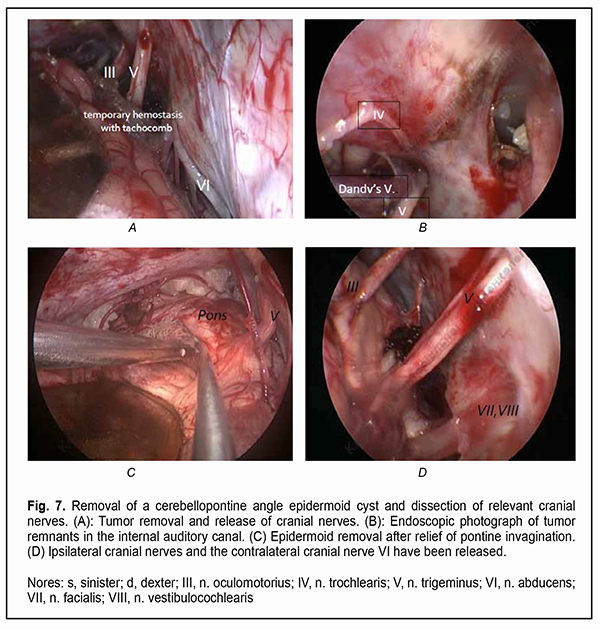

It is a common opinion that a total resection of the epidermoid cyst facilitates a prolonged period without relapse [4-10]. Incomplete cyst resection is associated with a significantly higher rate of epidermoid tumor recurrence compared to total resection [11, 12].. Since epidermoid cysts most commonly present at the fourth decade of life and recurrent symptoms can develop as late as 30-40 years after surgery, a total resection of the epidermoid cyst is not rational, especially in senile patients [10]. Others [13, 14, 15] reported a substantially shorter time to epidermoid recurrence, which is in agreement with our experience. On the one hand, because portions of the epidermoid capsule commonly become densely adherent to the surrounding neurovascular structures, making complete removal (and, consequently, achieving the maintenance of function of the cranial nerves, especially the ocular motor and ophthalmic nerves) challenging, a number of authors [11, 12, 16] advocate avoiding a total removal of the epidermoid cyst. Surgical intervention is usually aimed at making tumor excision as safe as possible, but dissecting the capsule away from the above nerves is challenging. Given the nature of tumor growth, the use of a neurosurgical microscope and an endoscopic approach and intraoperative monitoring of cranial nerves are necessary for the excision of skull base epidermoid cysts [10, 11, 17]. However, even a subtotal resection of the epidermoidal cyst may fail preventing aseptic meningitis with the cerebrospinal fluid characterized by negative bacterial cultures [18, 19]. Therefore, based on the literature, there is no unanimous opinion on whether an epidermoidal cyst should be totally removed or the adherent capsule should be left on the cranial nerves [5]. To the best of our knowledge, only a few cases of ophthalmological dysfunction in epidermoid cysts [20-26] and no data on the length of time required for recovery of visual and ocular motor functions after epidermoid removal have been reported. The purpose of the study was to assess longitudinal changes in neuro-ophthalmological abnormalities after surgery for skull base epidermoid cysts. Material and Methods We retrospectively reviewed the medical records of 21 patients (21 to 50 years; mean age, 35.2 ± 8.9 years) with skull base epidermoid cysts (predominantly, in the cerebellopontine angle or the parasellar region) who had either visual and ocular motor abnormalities or an involvement of the cranial nerves relevant to ophthalmological abnormalities, and had their cysts removed during the period from 2010 through 2020. Most patients (17/21) were of the young age (18-44 years), and the rest were of the middle age (45-59 years). The gender distribution was relatively equal (males constituted 42.85%). The House-Brackmann (HB) Grading System was used to assess the function of the facial nerve (CN VII), whereas the Barrow Neurological Institute Pain Scale (BNI-PS) and Barrow Neurological Institute Numbness Scale (BNI-NS), the function of the trigeminal nerve (CN V). Cyst location was determined based on preoperative T1w, T2w magnetic resonance imaging (MRI) and diffusion-weighted images (DWI) data. The location of the cranial nerves and their involvement in the neoplasm were verified using constructive interference in steady state 3 dimensional (CISS3D) on a 1.5-T Siemens MRI system or 3Ddrive on a 3.0-T Philips Achieva MRI system (Best, The Netherlands). Location of the epidermoid, location/involvement of the cranial nerves, presence and severity of adhesions of the cyst capsule to cranial nerves and/or the brainstem were assessed intra-operatively, which was video recorded by Sony HDR-PJ10 microscope camera and Karl Storz endoscope camera and documented in the protocol. A midline suboccipital and subtentorial approach was used for the epidermoid cysts of the fourth ventricle. Variations of the retrosigmoid approach used for the epidermoid cysts confined to the cerebellopontine angle depended on the extension of the epidermoid in the posterior fossa. Combined approaches were used if the lesion extended outside the posterior fossa into the middle fossa. The period from the onset of ophthalmological or neurological symptoms to surgery varied from one to 180 months. A neuro-ophthalmic examination included best-corrected visual acuity assessment, biomicroscopy, static automated and kinetic perimetry, and direct and indirect ophthalmoscopy. The amount of eye movement was determined for each of the four principal directions of gaze (as per Golovin) to determine the objective criteria for assessing the severity of the third, fourth and/or sixth cranial nerve lesions and changes in the recovery of oculomotor functions. The amount of eye movement was defined as normal (37° upward, 53° downward, 43° outward, or 46° inward), restricted (6° to 36° upward, 6° to 52° downward, 6° to 42° outward, or 6° to 45° inward), or no or almost no (0° to 5°) eye movement. The result of the study was presented as unimpaired ocular motility, restricted ocular motility or no ocular motility. Direct and consensual pupil response to light, and the size and symmetry of the pupils were assessed. Visual acuity was assessed with a diaphragm if there was mydriasis caused by CN III palsy. A Karl Zeiss OPMI MD stereo microscope equipped with Superlux 300 Fiber Optic Illumination System (Karl Zeiss Microscopy Deutschland GmbH, Oberkochen, Germany); a 4-mm/2.7-mm, 30-degree/45-degree KARL STORZ Hopkins II endoscope (Karl Storz GmbH & Co., Tuttlingen, Germany) and nerve integrity monitor (NIM-Response 3.0 System, Medtronic Xomed, Jacksonville, Florida) were used during epidermoid removal according to the routine methodology for the oculomotor nerves. Electrodes were placed on the CN III, IV, V, VI and VII, and switched over to the relevant nerve during a surgical procedure. The highest available microscope magnification (24х) was used while guiding the capsule away from the vessels, brainstem and nerves. In addition, an endoscope with a 30-degree or 45-degree viewing angle was used for examining the areas that would otherwise be difficult to view (Fig. 7).

Of the 21 patients, 7 (33.33%) had a gross total removal and 2 (9.53%) had a near total removal of the cyst, with residual capsule fragments not exceeding 2-3 mm (Figs. 4, 5, 6, and 7). In addition, 12 (57.14%) had a subtotal removal of the cyst, with either intraoperative evidence of residual capsule fragments measuring from 2 mm to 10 mm, or postoperative MRI evidence of residual capsule fragments not exceeding 11 mm in the largest dimension. The capsule adhesion to surrounding neurocascular structure at the location where the dissection was difficult was seen in 18 patients (85.7%). In some cases, this can lead to the impossibility of safe total capsule dissection from the brainstem and cranial nerves. Postoperative follow-up ranged from 1 to 12 years, with mean and median values of 38.5 ± 4.8 months and 24 months, respectively (Fig. 8).